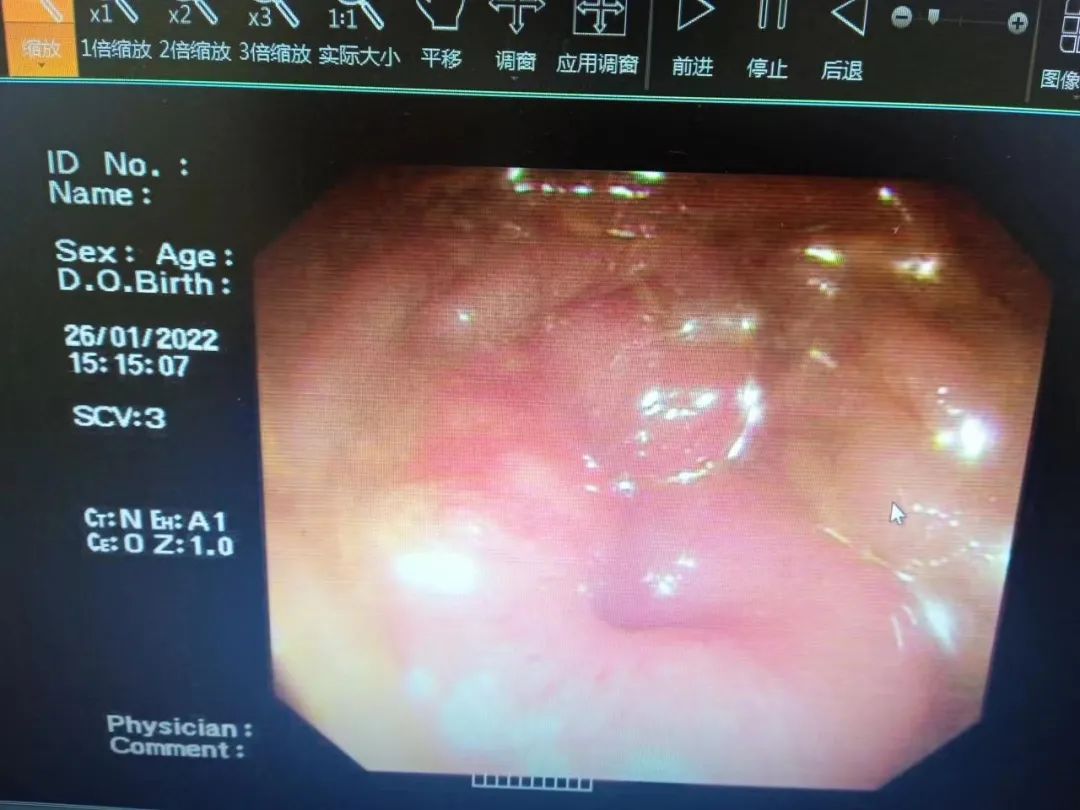

然而,内镜下见结肠近肝区处狭窄,镜身不能通过,加之老人年纪大、身体状况不佳,对医生来说,这项手术无疑是一次巨大的挑战。

手术前,李明峰主任带领团队做了充分的肠道准备工作,将病人的胸腹水、肾功能等相关情况进行改善。1 月 27 日下午,消化内科胃镜室医护人员正式开始为吴奶奶行手术。由于吴奶奶已经近一个月不进食、不排便,肠道内的粪水味道异常浓烈,医务人员屏住恶臭,经过反复冲洗,终于将肠镜插进了升结肠,发现巨大的肿瘤占据整个肠腔,没有缝隙。

李明峰主任凭借多年来丰富的临床经验,在多次尝试的情况下终于将斑马导丝顺利通过狭窄段,在内镜的支持下最终将结肠支架置入成功,整个操作过程顺利。虽然手术经历了很长时间,但当支架置入成功的那一刻,堵在肠道内的大量粪便喷涌而出,在场的所有医务人员激动万分,完全忘记了手术过程中的艰难,也完全忽略了这股常人难以忍受的味道。